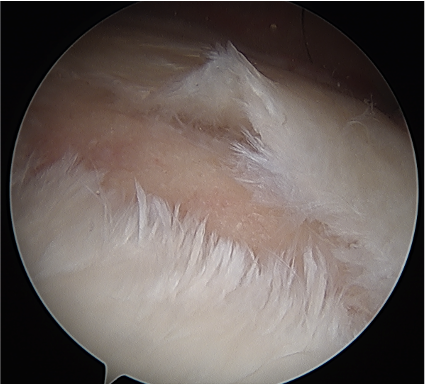

Subacromial space approach

Ghodadra et al Arthroscopy 2009

- subacromial space

- identify spine of scapula and dissect between infraspinatous and supraspinatous

- accessory posterior portal, retract IS and nerve

- decompress with shaver

Subacromial space approach to cyst decompression